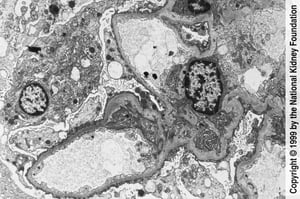

In der Transmissionselektronenmikroskopie (×3000) ist eine weitgehende Abstumpfung und Auslöschung der Podozyten zu erkennen.

In der Transmissionselektronenmikroskopie (×3000) ist eine weitgehende Abstumpfung und Auslöschung der Podozyten zu erk

Image provided by Agnes Fogo, MD, and the American Journal of Kidney Diseases' Atlas of Renal Pathology (see www.ajkd.org).